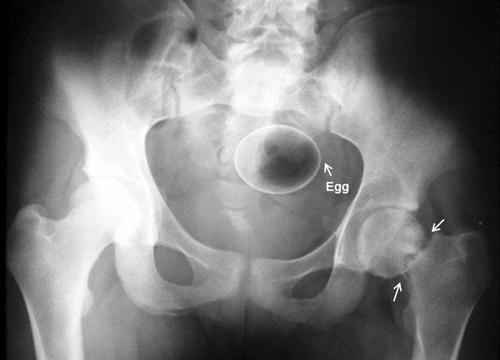

Una mención especial merece la colección de radiografías correspondientes a elementos extraños insertados voluntariamente en el cuerpo, como botes de desodorante, botellas de bebida energética, frutas y verduras o hasta un huevo son algunos de los casos que los autores de la Radiopaedia han compartido.

Una vez la berengena ingresó en el cuerpo de esta persona, no hubo forma de recuperarla. El avergonzado personaje tuvo que presentarse en el hospital para resolver su problema.